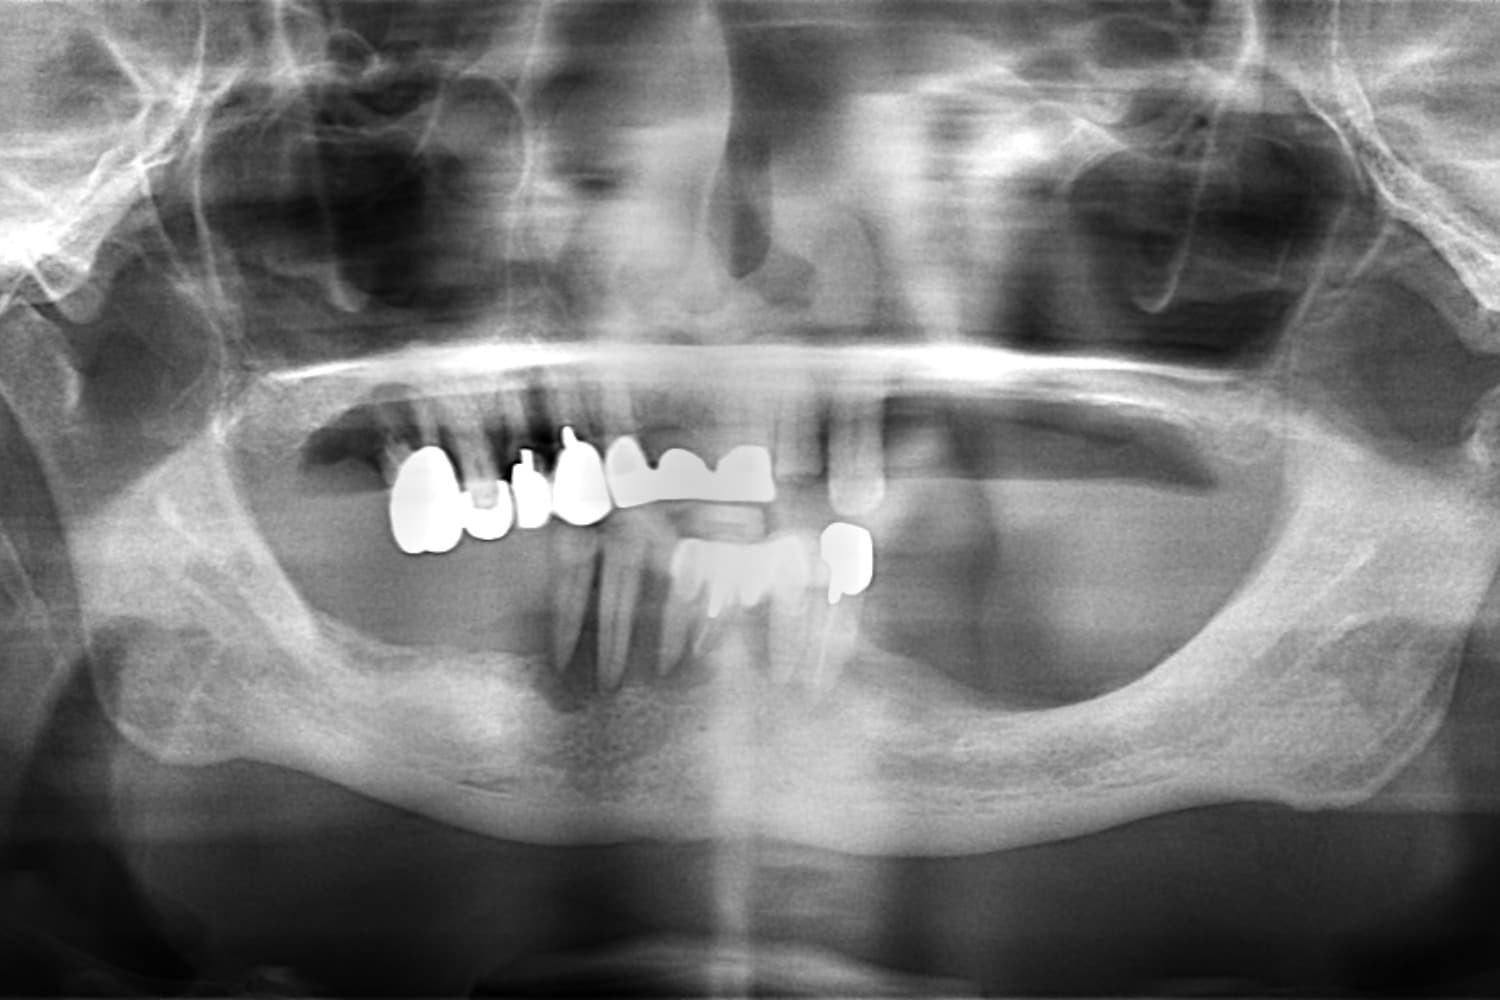

Before

重度の歯周病で上下すべての歯を抜歯せざるを得なくなった患者さまに対して、上下顎オールオン4で治療を行った。

年齢

70代

性別

男性

主訴

入れ歯が合わない 噛みにくい

治療期間

6カ月

治療回数

15回

費用

7,432,000円

副作用・リスク

清掃状態等により将来炎症を起こす可能性があります。